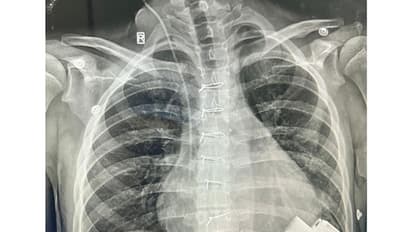

After a complex and difficult surgery that involved connecting a Mechanical Heart Pump to the main pumping chamber of the heart and then connecting the other end (outflow) to the Aorta - the artery that takes blood to various organs of the body. The whole pump is so small that it sits inside the chest and connects to a computerised controller and battery through a small wire that comes out of the skin. As the device was started, it pumped blood from the left ventricle to the body and within a few days in the Pediatric Cardiac ICU, his organ functions started recovering.

After surgery, he has made an extraordinary recovery, from being limited to bed most of the times, he is now walking, going up and down the stairs, has been discharged from the hospital and soon is expecedt to return to his country, go to school, play but with a controller and a battery to remind him of how strong he and his family has been through this dangerous illness.